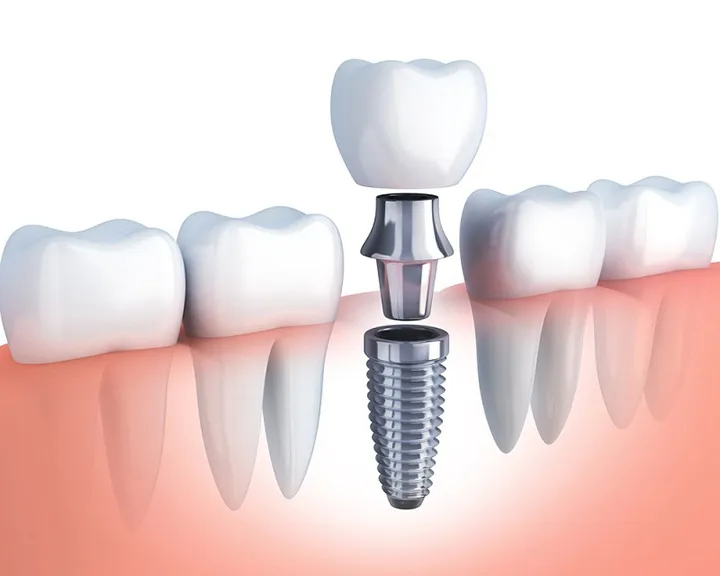

Cấy xương răng là kỹ thuật bổ sung xương vào hàm, nhằm mục đích tái tạo và làm tăng thể tích của xương hàm, tăng độ rắn chắc, giúp nâng đỡ trụ Implant khi trồng răng giả cố định.

Kỹ thuật này sẽ được thực hiện trước khi đặt trụ Implant khoảng 9 – 12 tháng, để đảm bảo xương mới tương thích và ổn định trong cơ thể. Khi xương đã đủ cứng chắc, bạn sẽ được tiến hành đặt trụ Implant và thực hiện các bước tiếp theo.